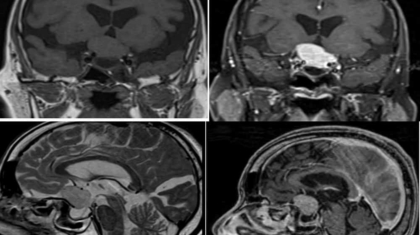

An elderly woman presented with complaints of progressive diminution of vision in both eyes. MRI showed suprasellar meningioma impinging on the optic chiasm. Patient underwent excision of the mass .

Post operatively the patient did not wake up from anaesthesia.

CT scan was ordered to look for post-operative complications.